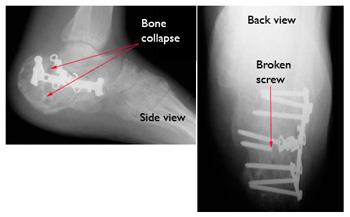

Surgical treatment of calcaneus fractures usually involves making an incision over the outside of the foot and placing a metal plate and screws into the broken heel bone. In this Ask Dr. They can relieve you from the pain felt and you can always get stylish.

A calcaneal stress fracture is one or more small breaks in your. A plate andor screws may be used to hold the pieces of the fracture in place. However most often a broken heel requires surgery.